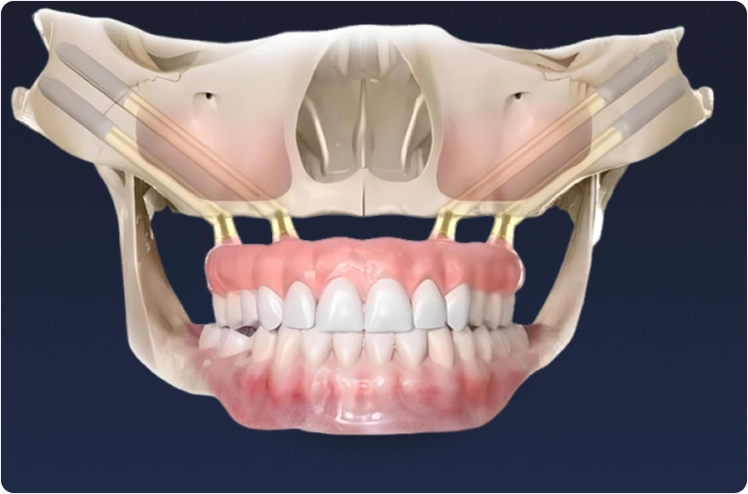

Mentoria individual com planejamento 3D, instrução operatória e acompanhamento cirúrgico hospitalar para implantodontistas que atuam com All-on-Four, Pterigóide e Zigomático.

Cirurgião-Dentista há 38 anos, referência nacional em reabilitação de maxilas atróficas.

Atuou com centenas de casos envolvendo carga imediata, pterigoides, zigomáticos e protocolos híbridos.